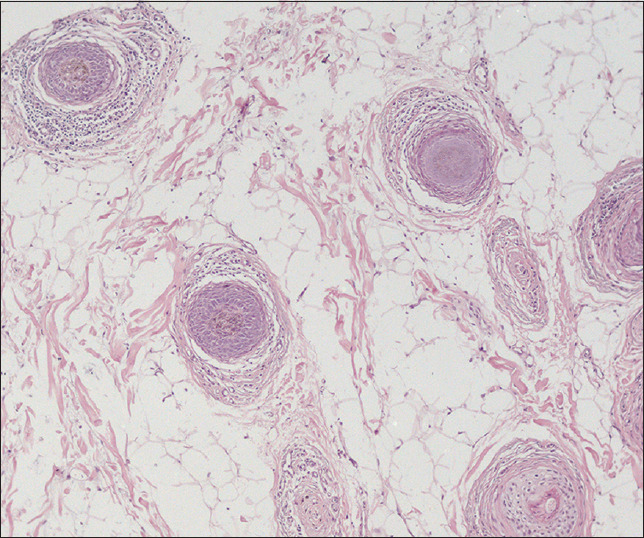

一名 39 岁的男性患者主诉头皮头发突然开始逐渐变白。患者从发现自己的头发开始变白的那一刻起,就经常自拍,记录下了这一情况。根据临床、皮肤镜、组织病理学和免疫荧光检查结果,诊断为色素性脱发。随访 6 个月后,观察到色素头发完全再生,无需任何系统治疗。

A 39-year-old male presented with the complaint of sudden onset and progressive whitening of the scalp hair. The patient documented the situation by regularly taking selfies starting from the moment he noticed that his hair was starting to turn white. A diagnosis of alopecia areata involving pigmented hair was made with clinical, dermoscopic, histopathological, and immunofluorescence findings. Total regrowth of the pigmented hair was observed at 6 months follow-up without any systemic treatment.